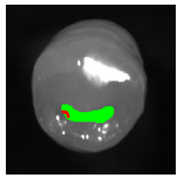

Classification and statistical analysis: Using custom MATLAB® (MathWorks, Natick, MA, USA) code, a graphical user interface (GUI) for reading, visualizing and selecting hyperspectral data was developed. Within this GUI, ten data points in close proximity to the histologically validated region were selected manually for each tooth (Figure 2a). The corresponding reflectance spectra were saved for further processing and associated with the histological occlusal state by binarization (0 = stained, 1 = stained lesion). The number of teeth and spectra within each occlusal health state group is shown in Table 1. In order to remove potential noise from the spectra, an additional second dataset was generated by applying a Savitzky–Golay filter (order = 2, frame length = 7) to the selected raw reflectance spectra (Figure 2b). The Savitzky–Golay filter is well established in (hyper)spectral data analysis because it enables an increase in data precision without distorting the underlying signal [30]. Intensities at the wavelengths 505–525 nm were eliminated due to the high noise level of the camera sensor in this region.

Figure 2.

(a) HSI spectra were selected (white crosses) within the central fissure near the histological cross-sectional plane (dashed line) and (b) preprocessed, including (i) the elimination of wavelengths with high noise (505–525 nm; shaded red) and (ii) filtering of spectra to find the optimal data configuration for classifier training.